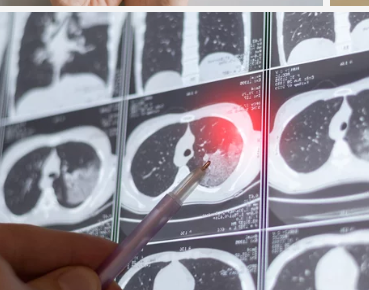

3. 폐기흉의 치료 방법 – 경미한 경우 & 중증 치료 차이

② 중증 폐기흉 – 흉관 삽입(공기 배출 치료)

✔ 폐가 심하게 눌려 있거나 호흡 곤란이 심할 경우, 흉관 삽입이 필요

✔ 가슴에 관을 삽입하여 폐 주위에 찬 공기를 배출(흉관 삽입술)

✔ 대부분 2~5일간 흉관을 유지하면서 폐가 정상적으로 펴지는지 확인